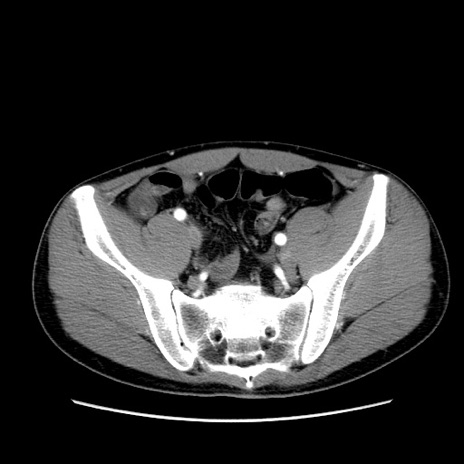

症例36(横断像)

【症例】20歳代 男性

【主訴】心窩部痛

【現病歴】今朝より上腹部痛あり。一旦軽快していたが再度出現したため救急要請。昨日夕に白身の魚を含む刺身を食べた。

【身体所見】BP 136/89mmHg、HR 74/min、BT 37.0℃、腹部:膨満、軟、心窩部に圧痛あり。反跳痛なし、筋性防御なし、腸雑音やや亢進あり。

【データ】WBC 17700、CRP 0.48